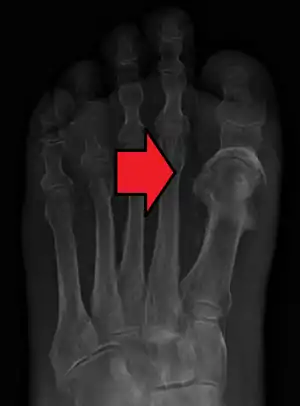

![]() | |

| Microscopic section of the lungs showing a blood vessel with fibrinoid material and an empty space indicative of the presence of lipid dissolved during the staining process. Haematoxylin and eosin stain | |